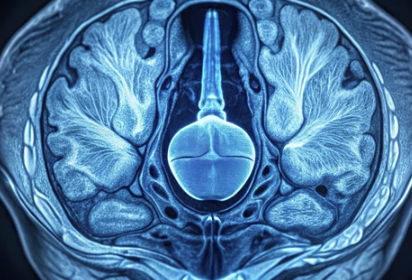

전립선은 남성 생식기 중 하나로, 방광 아래에 위치해 요도를 둘러싸고 있습니다. 주요 역할은 정액의 일부를 생성해 정자의 이동을 돕는 것입니다.

전립선이 비정상적으로 커지면서 요도를 압박하고 소변 흐름에 장애를 일으키는 상태입니다. 이는 비암성(양성) 질환으로, 암과는 관련이 없습니다.